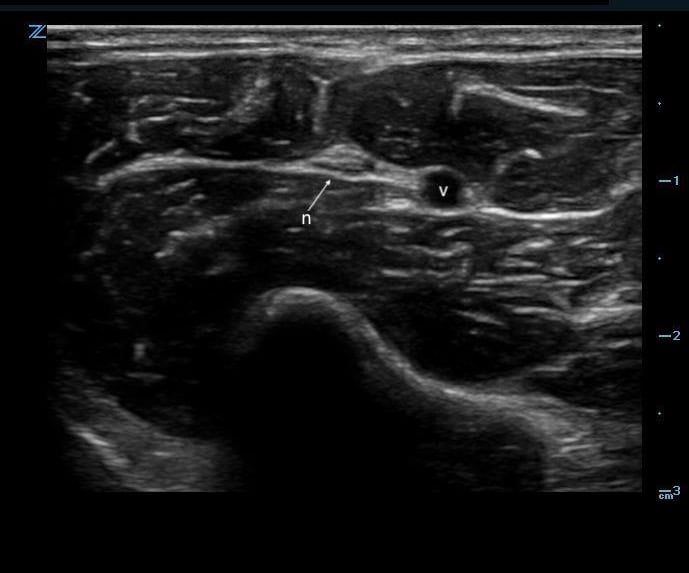

Video 3. Artery/vein color doppler - Nerves may run adjacent to deeper vascular bundles and appear as hyperechoic, honeycomb pattern structures in transverse view.

- Figure 3. Nerve adjacent to a vessel